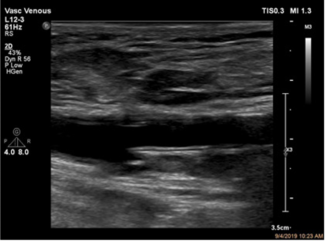

This analysis describes the technique of ultrasound-assisted percutaneous superficial femoral arterial access closure with a Mynx device (Cordis).